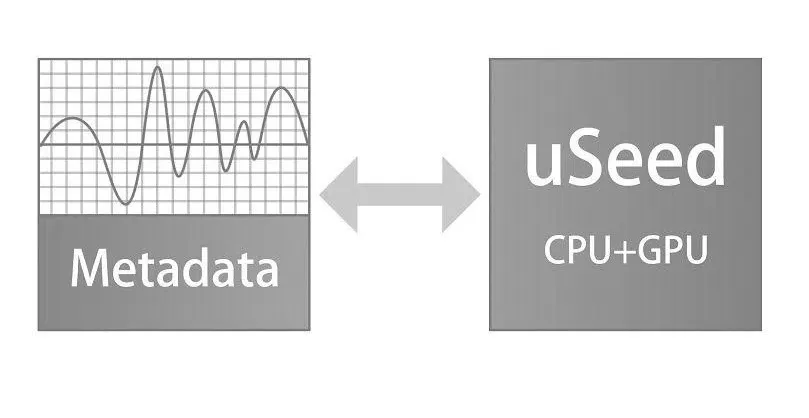

uSeed

Изображения в платформе uSeed сохраняются в виде метаданных для последующей обработки с использованием технологии параллельных вычислений CPU + GPU. Многократно повышена производительность системы и частота кадров при формировании изображений